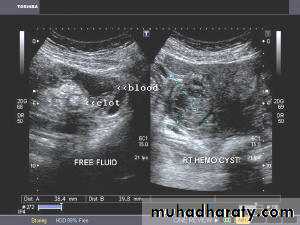

Hemorrhagic ovarian cysts:

Hemorrhagic cyst of ovary with ruptured ectopic pregnancy:

This female patient has a left ovarian hemorrhagic cyst (see ultrasound image above-left). In addition, there is a large collection of free fluid with particulate matter in the pelvis. The right fallopian tube is thickened with a ring shaped mass. This suggests that there is significant hemorrhage into the pelvis due to a ruptured ectopic pregnancy (right tubal ectopic gestation). The left ovarian hemorrhagic cyst appears intact, ruling out ruptured hemorrhagic cyst.